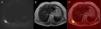

A) La secuencia ponderada en difusión (valor b = 600) muestra una masa de intensa restricción en la región subescapular inferior derecha entre la escápula y la pared torácica. B) La masa se caracteriza por una isointensidad de señal moderadamente heterogénea en T2. C) La fusión de la secuencia ponderada en T2 demuestra más claramente la intensa restricción en la masa.

La paciente era una mujer de 41 años de edad con diagnóstico de carcinoma tímico, tratado con quimioterapia y radioterapia. La TC torácica mostró una masa mediastínica anterior que no se modificó después del tratamiento. Más tarde la paciente se sometió a una RM torácica que no mostró signos de actividad de la masa mediastínica tanto con realce de contraste como con restricción de difusión. Sin embargo, se observó otra masa en la región subescapular inferior derecha entre la escápula y la pared torácica. La masa se asociaba a una baja intensidad de señal en T1 y T2 y una restricción moderadamente heterogénea e intensa en las secuencias ponderadas en difusión (Fig. 1). La masa era estable, si se la comparaba con los exámenes previos. El examen histopatológico demostró estrías de tejido graso que alternaban con fibras de tejido fibroso. El tejido fibroso hipertrófico contenía material fibrilar con afinidades de tinción idénticas al tejido fibroso necrótico, músculo y grasa. Estos hallazgos eran compatibles con un ED.